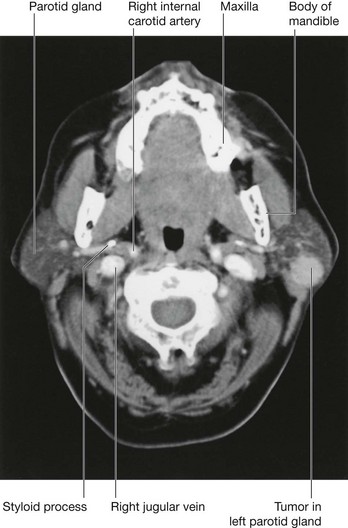

Tumors of the parotid gland

The commonest tumors of the parotid gland (Fig. 8.57) are benign and typically involve the superficial gland. These include pleomorphic adenoma and adenolymphoma. Their importance is in relation to their anatomical position. Critically, the relationship of the tumor to the branches of the facial nerve [VII] must be defined because resection may damage the facial nerve [VII]. In addition, if the tumor extends to the deep part of the gland the patient will need to provide consent for potential facial nerve [VII] damage.

image

Fig. 8.57 Tumor in parotid gland. Axial CT scan.